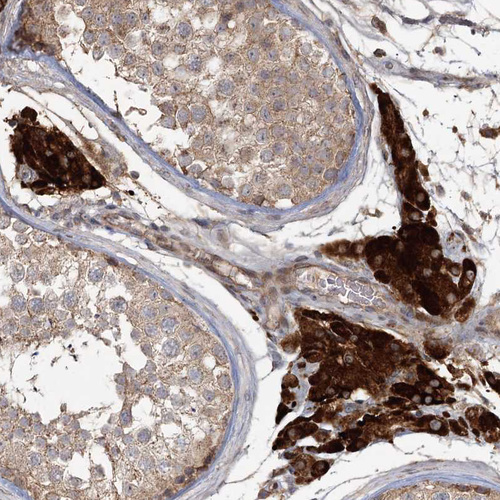

Immunohistochemical staining of human heart muscle shows moderate cytoplasmic positivity in cardiomyocytes.